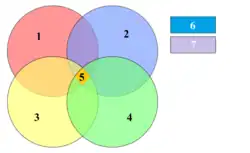

Four things are required for caries to form: a tooth surface (enamel or dentin), caries-causing bacteria, fermentable carbohydrates (such as sucrose), and time.[20] This involves adherence of food to the teeth and acid creation by the bacteria that makes up the dental plaque.[21] However, these four criteria are not always enough to cause the disease and a sheltered environment promoting development of a cariogenic biofilm is required. The caries disease process does not have an inevitable outcome, and different individuals will be susceptible to different degrees depending on the shape of their teeth, oral hygiene habits, and the buffering capacity of their saliva. Dental caries can occur on any surface of a tooth that is exposed to the oral cavity, but not the structures that are retained within the bone.[22]

Bacteria

The most common bacteria associated with dental cavities are the mutans streptococci, most prominently Streptococcus mutans and Streptococcus sobrinus, and lactobacilli. However, cariogenic bacteria (the ones that can cause the disease) are present in dental plaque. They are usually in concentrations too low to cause problems unless there is a shift in the balance.[27] This is driven by local environmental change, such as frequent sugar intake or inadequate biofilm removal (toothbrushing).[28] If left untreated, the disease can lead to pain, tooth loss and infection.[29]

The mouth contains a wide variety of oral bacteria. Only a few specific species of bacteria are believed to cause dental caries: Streptococcus mutans and Lactobacillus species among them. Streptococcus mutans are gram-positive bacteria that constitute biofilms on the surface of teeth. These organisms can produce high levels of lactic acid following fermentation of dietary sugars and are resistant to the adverse effects of low pH, properties essential for cariogenic bacteria.[24] As the cementum of root surfaces is more easily demineralized than enamel surfaces, a wider variety of bacteria can cause root caries, including Lactobacillus acidophilus, Actinomyces spp., Nocardia spp., and Streptococcus mutans. Bacteria collect around the teeth and gums in a sticky, creamy-coloured mass called plaque, which serves as a biofilm. Some sites collect plaque more commonly than others, for example, sites with a low rate of salivary flow (molar fissures). Grooves on the occlusal surfaces of molar and premolar teeth provide microscopic retention sites for plaque bacteria, as do the interproximal sites. Plaque may also collect above or below the gingiva, where it is referred to as supra- or sub-gingival plaque, respectively.